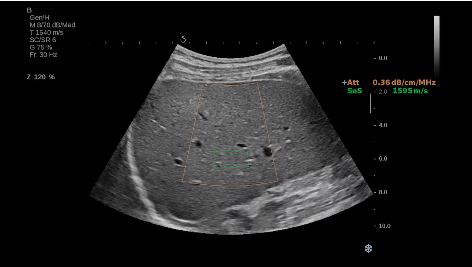

法國聲科影像(SuperSonic Imagine,SSI. Euroniex:FR0010526814)近日發(fā)表公告,宣布其研發(fā)的新一代“極速”超聲成像平臺(UltraFast Imaging),首次實(shí)現(xiàn)了肝臟的多項(xiàng)超聲定量評估新指標(biāo)同步檢測,包括:Att PLUS,SSp PLUS和Vi PLUS等,基本涵蓋肝臟相關(guān)病理變化指征的如纖維化、脂肪變、炎癥等。據(jù)悉,此多項(xiàng)新技術(shù)新將搭載于新Aixplorer系列E超系統(tǒng)。

E超相關(guān)技術(shù)已被多項(xiàng)多中心大樣本研究證實(shí)對于肝纖維化無創(chuàng)評估有重要意義,同時(shí)也可全面應(yīng)用于乳腺、甲狀腺、肝臟、前列腺、肌骨、婦科等全身各組織器官的定量評估和鑒別診斷。在慢性肝臟方面,聲科E超的肝臟相關(guān)定量診斷技術(shù)集,于2018年獲得美國FDA認(rèn)證,成為FDA歷史上首次獲批的單病種超聲全面定量解決方案。